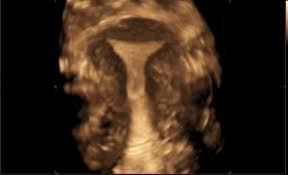

Female pelvis ultrasound sonography plays the primary role in imaging of the female pelvis. Primary indications for female pelvic us examination are pelvic pain, abnormal vaginal bleeding, and suspicion of pelvic mass. An ultrasound of the female pelvis may be performed by examination of the abdomen, called transabdominal, or by using a special probe designed to be inserted into the vagina, called transvaginal. Ultrasound imaging uses soundwaves to create pictures of the inside of the body. However, it is considered more invasive than the transabdominal approach. • normal and ectopic pregnancy implantation can be accurately Within the right ovary, there is a 2.5 cm thick walled cyst with crenulated inner margin and peripheral vascularity consistent with a corpus luteum. A transabdominal (ta) evaluation and a transvaginal (tv) / endovaginal (ev) evaluation. Further charac terization of a pelvic abnormality noted on another imaging study 14. A pelvic ultrasound is a noninvasive diagnostic exam that produces images that are used to assess organs and structures within the female pelvis. Measurements should be recorded for simple/complex/dermoid cysts. Transvaginal ultrasound is a test used to look at a woman's uterus, ovaries, tubes, cervix and pelvic area. Both ovaries should be identified and measured if appropriate again in 3 planes.

Complete pelvic ultrasound (upeltv) this is a complete pelvic ultrasound exam, including transabdominal and transvaginal. If a male sonographer is doing the scan, there will need to be a female chaperone present for the transvaginal or translabial portion of the exam. Normal pelvic ultrasound nazari l, assistant professor ob/gyn shahid beheshti university of medical sciences. The endometrial stripe measures __ cm in diameter and is normal in echogenicity. The sound waves create a picture on a video monitor.